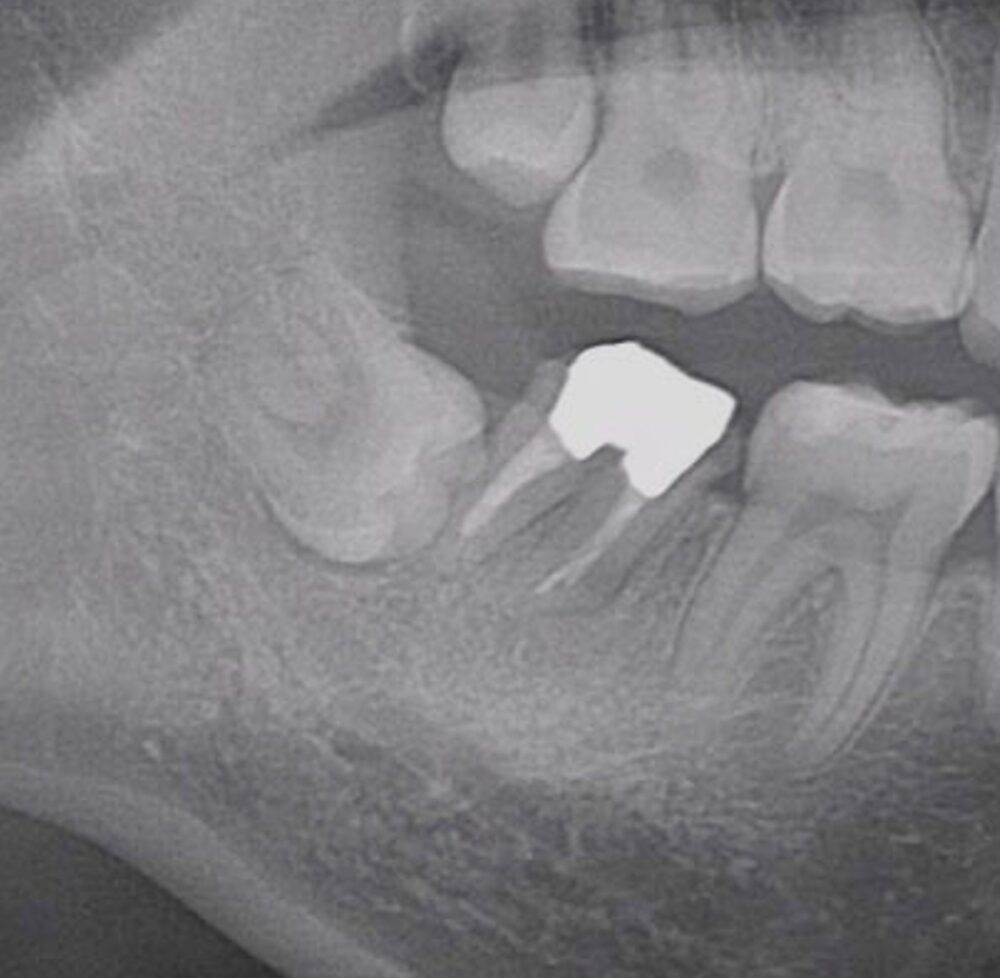

症例2

| 患者様データ | 40代 男性 |

| 来院時の主訴 | 「左下が痛くて噛めない。」 |

| 医院の診断 | 左下第一大臼歯歯根破折、慢性根尖性歯周炎 |

| 通院期間 | 6か月 |

| 来院回数 | 9回 |

| 治療費 | 総額:275,000円(税抜) 【内訳】 歯牙移植150,000円、ファイバーポストコア20,000円、セラミック治療85,000円、歯頸部ダイレクトボンディング10,000円×2 |

| リスクと副作用 | ①根管治療歯は長期的には破折するリスク ②長期的なメインテナンスが必要 ③歯根の外部吸収 |

| ここがこだわりのポイント!☝ |

抜歯が必要になった際に余っている親知らずがあれば移植歯として利用することができます。 術前に撮影したCT画像から3Dプリンターを用いて親知らずのレプリカを作製することで、親知らずが乾燥することを防ぎ、成功率が上がるよう努力しています。 |